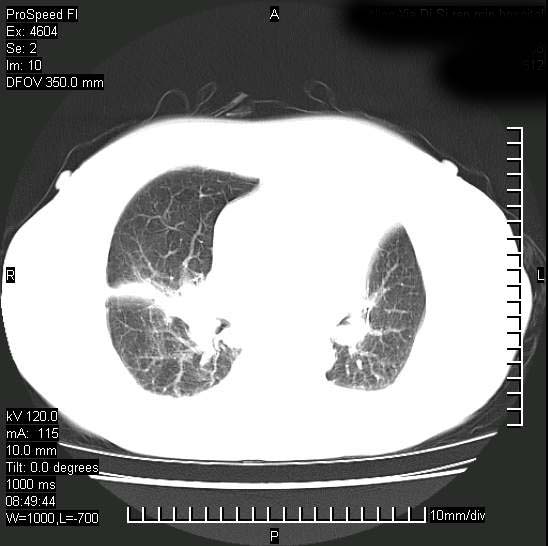

十几年前曾患肺结核,一周前突咳血约100ml,中性粒细胞稍高,诊断两上肺陈旧结核,下肺炎症,给予抗炎治疗,近几日晚上高热,39度,仍咳少量血,4天前ct及今天ct上传。

今天ct

短短几天内,病变范围明显增多扩大,以左侧明显,而且双侧出现胸水,还是考虑感染.

短短几天内,病变范围明显增多扩大,以左侧明显,而且双侧出现胸水,我更多考虑左侧中心性肺癌并并阻塞性不张及肺炎,炎症变化也太快了!

无论是肿瘤还是炎症4天的时间都发展够快的,并且还在治疗中,如果说是左肺癌那么右肺的病变不好解释,本人更加倾向于炎症,左肺舌叶支气管被痰栓或血凝块堵塞,造成阻塞性肺炎。

1)两肺结核并感染。2)不排除左肺上叶中央型肺癌并阻塞性肺炎、肺不张可能;建议行纤支镜检查。3)右肺门及纵隔淋巴结肿大。4)双侧胸腔积液。

陈旧性肺结核及左下肺不张,咯血后肺部感染,双胸腔积液,高热可能与痰液引流不畅有关。